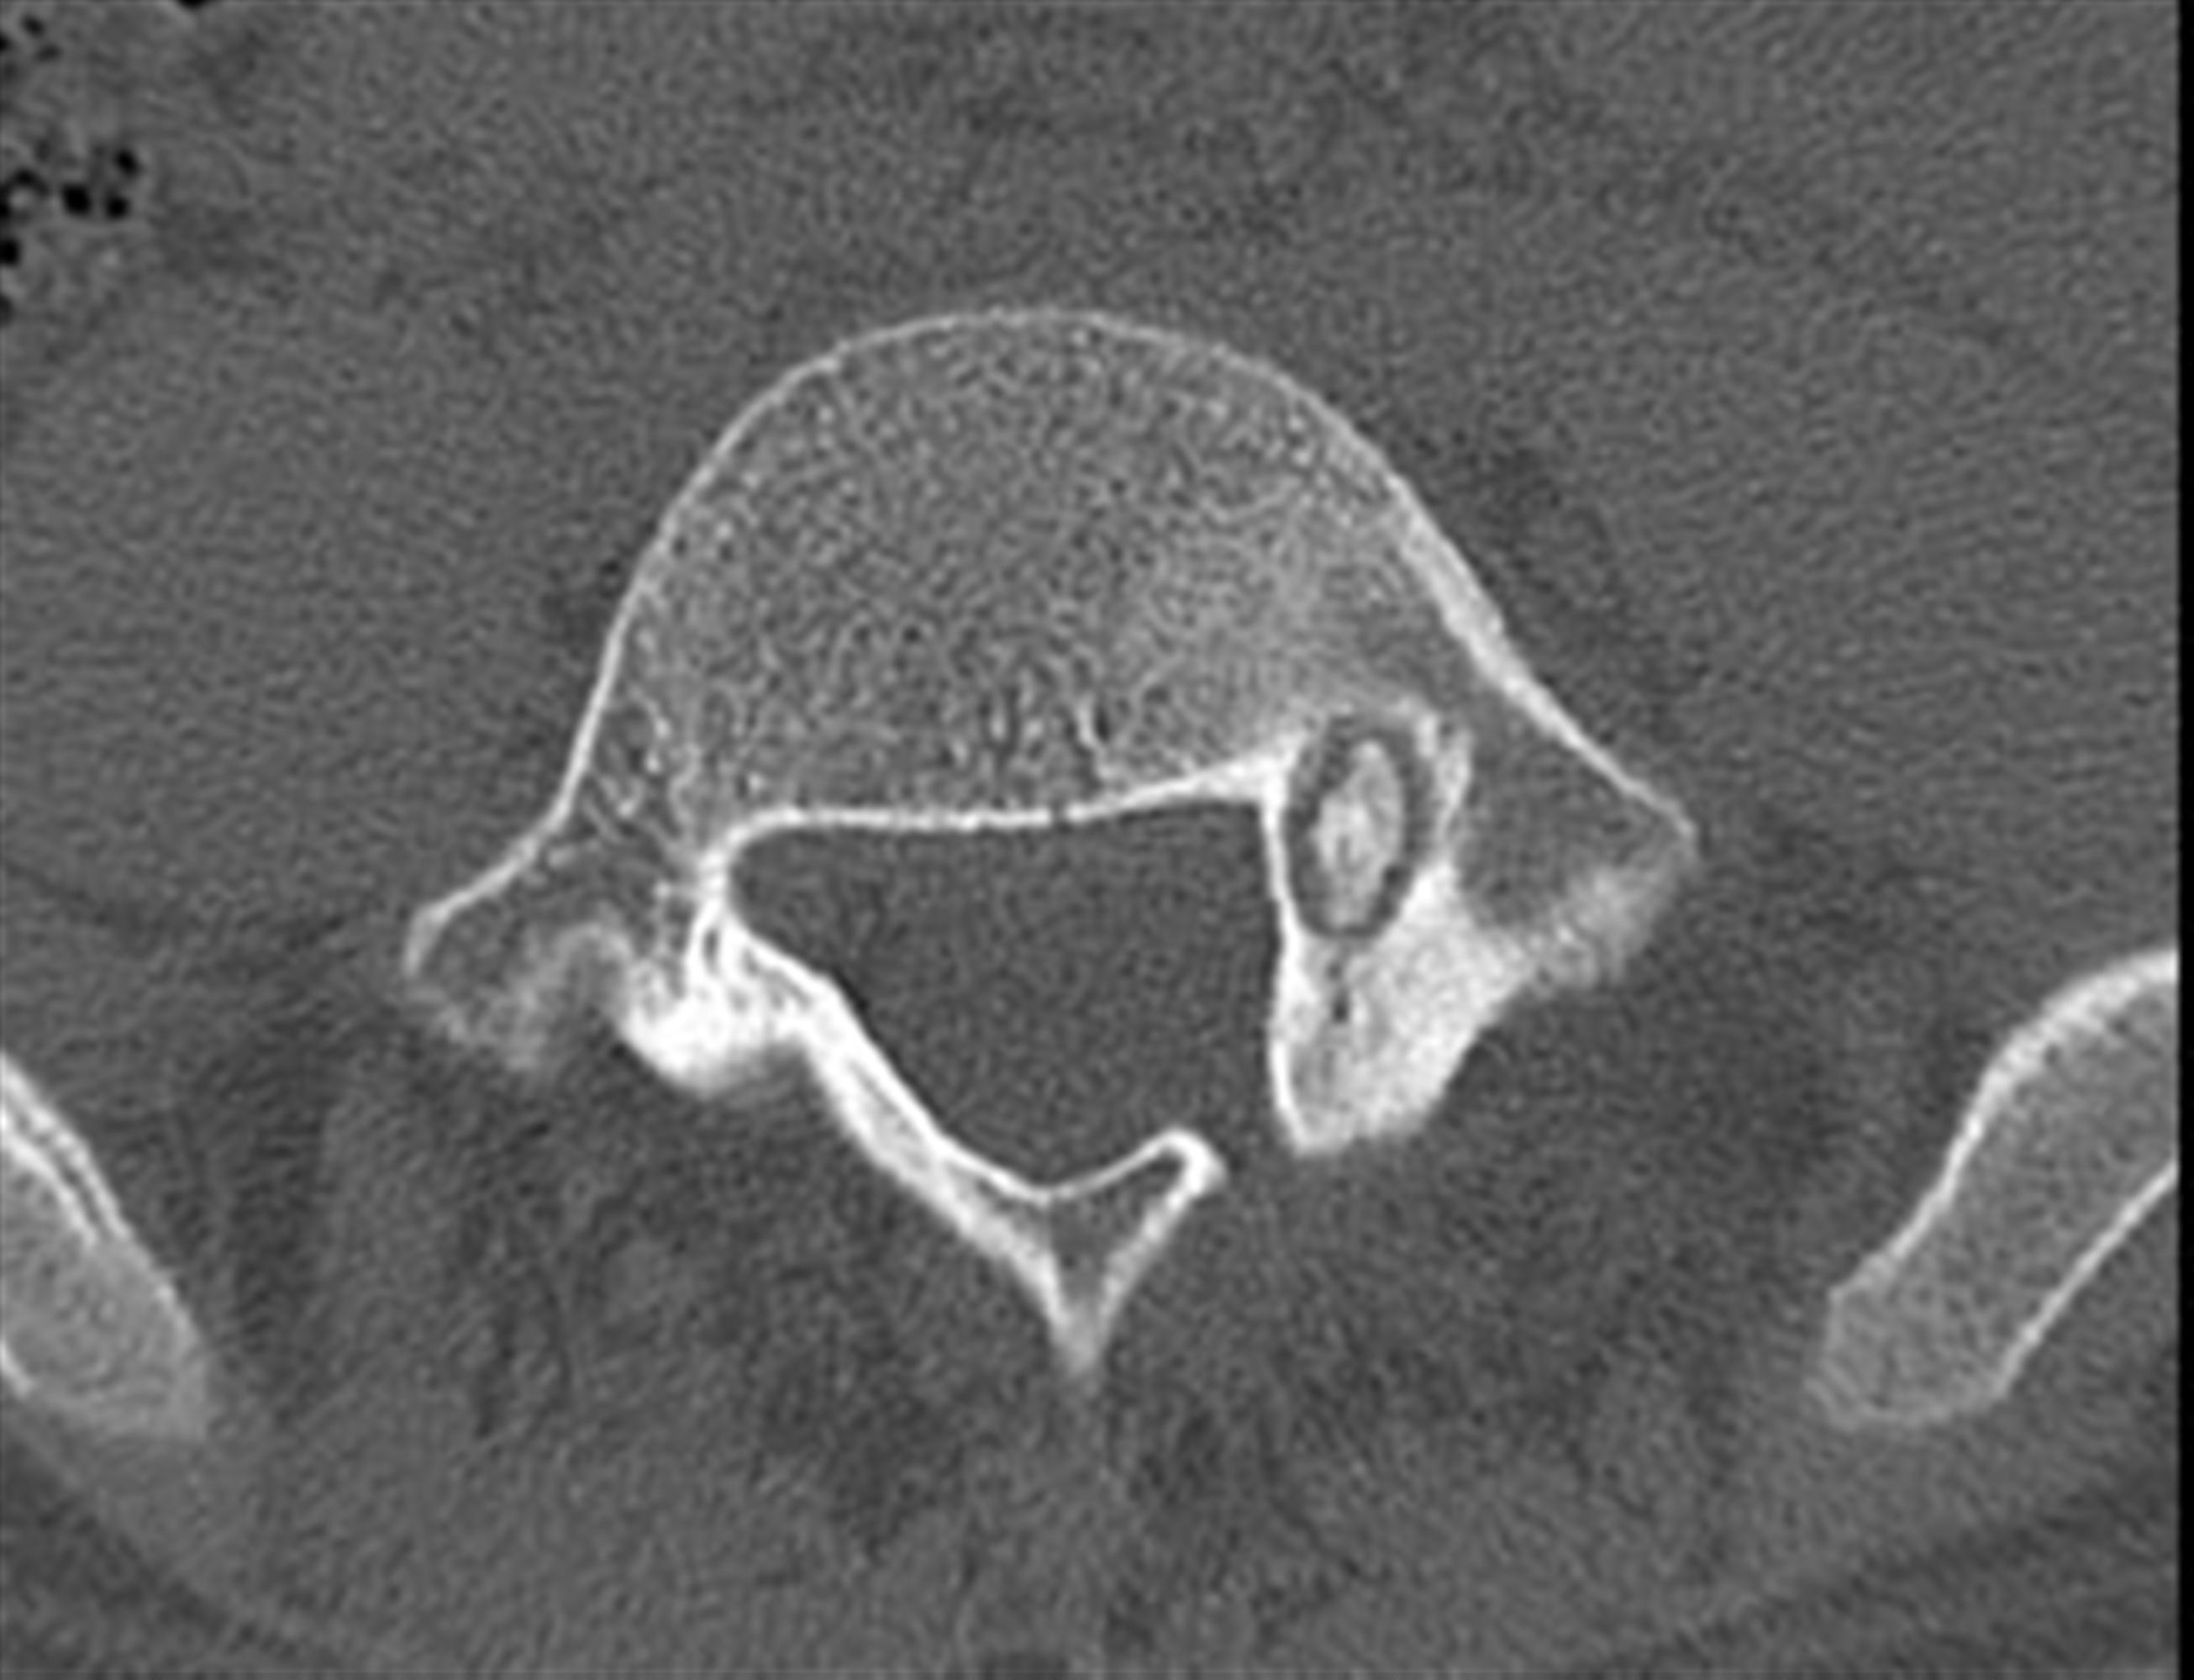

ankylosing spondylitis has a high risk of…

osteopenia/porosis due to increased osteoclast activity in the setting of chronic inflamation (il 6, tnf-a)

so have low threshhold for suspicion of vertebral fracture after a fall